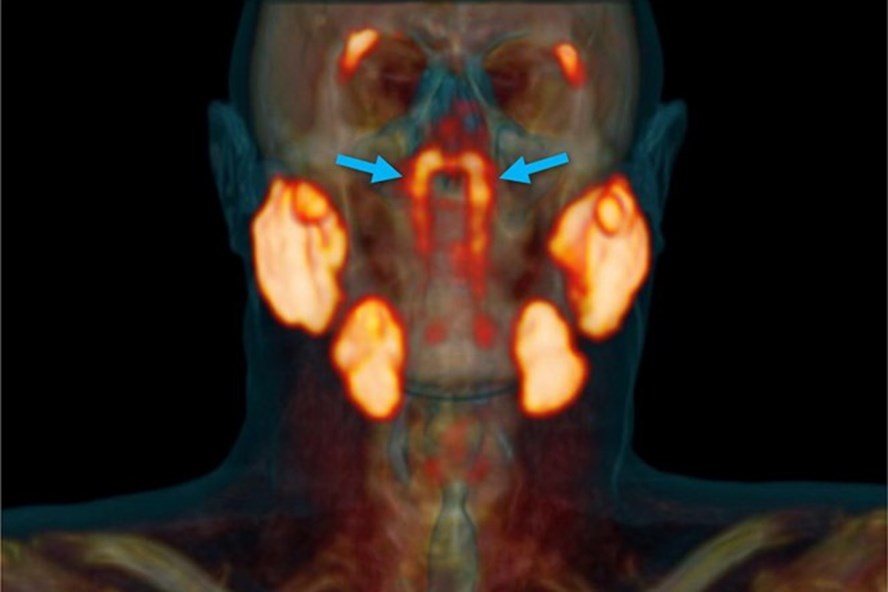

Các nhà nghiên cứu tại Viện ung thư Hà Lan phát hiện thêm cặp tuyến nước bọt thứ tư, nằm ở nơi khoang mũi nối với cổ họng.

Cặp tuyến nước bọt thứ tư được các bác sĩ Hà Lan phát hiện nằm ở nơi khoang mũi nối với cổ họng. Ảnh: NY Post

Tiến sĩ Matthijs Valstar - tác giả của nghiên cứu - cùng các đồng nghiệp phát hiện ra trong khi nghiên cứu các bản chụp cắt lớp hộp sọ. Bản chụp cắt lớp cho thấy ở giữa hộp sọ là hai cấu trúc mô hẹp nằm ngay trên ống eustachian, nối giữa tai với cổ họng.